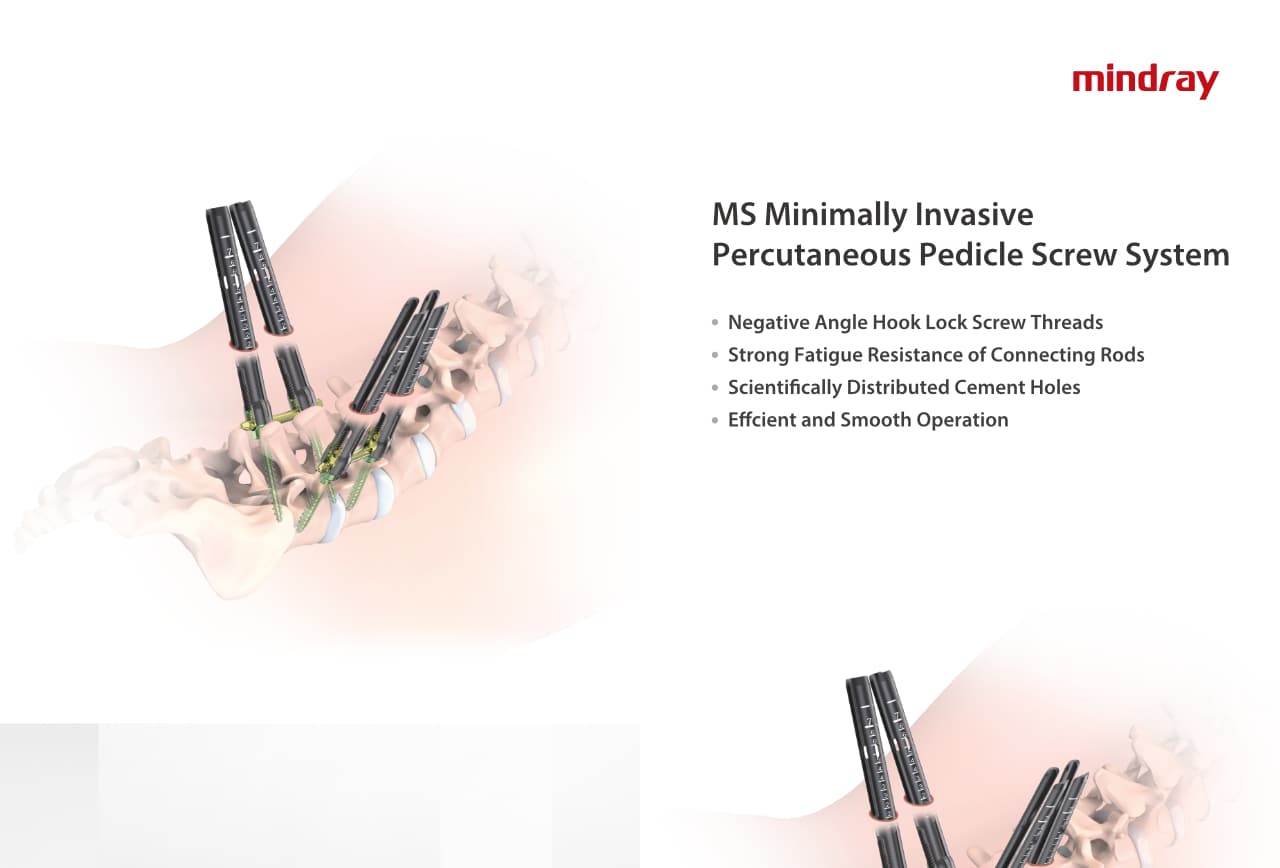

–Ю—А—В–Њ–њ–µ–і–Є—З–µ—Б–Ї–Њ–µ –њ–Њ–і—А–∞–Ј–і–µ–ї–µ–љ–Є–µ –Ї–Њ–Љ–њ–∞–љ–Є–Є Mindray, —А–∞—Б–њ–Њ–ї–Њ–ґ–µ–љ–љ–Њ–µ –≤ –£—Е–∞–љ–µ, —П–≤–ї—П–µ—В—Б—П –Њ–і–љ–Є–Љ –Є–Ј –≤–µ–і—Г—Й–Є—Е –њ—А–Њ–Є–Ј–≤–Њ–і–Є—В–µ–ї–µ–є –Њ—А—В–Њ–њ–µ–і–Є—З–µ—Б–Ї–Њ–є –њ—А–Њ–і—Г–Ї—Ж–Є–Є –Є–Ј –Ъ–Є—В–∞—П. –Ю–љ–Њ –Ј–∞–љ–Є–Љ–∞–µ—В—Б—П –Є—Б—Б–ї–µ–і–Њ–≤–∞–љ–Є—П–Љ–Є –Є —А–∞–Ј—А–∞–±–Њ—В–Ї–Њ–є, –њ—А–Њ–Є–Ј–≤–Њ–і—Б—В–≤–Њ–Љ –Є –Љ–∞—А–Ї–µ—В–Є–љ–≥–Њ–Љ —В—А–∞–≤–Љ–∞—В–Њ–ї–Њ–≥–Є—З–µ—Б–Ї–Є—Е –Є —Б–њ–Є–љ–∞–ї—М–љ—Л—Е –Є–Ј–і–µ–ї–Є–є, –њ—А–Њ–і—Г–Ї—Ж–Є–Є –і–ї—П –∞—А—В—А–Њ–њ–ї–∞—Б—В–Є–Ї–Є –Є –і—А—Г–≥–Є—Е —Е–Є—А—Г—А–≥–Є—З–µ—Б–Ї–Є—Е –Є–Ј–і–µ–ї–Є–є. –° –Љ–Њ–Љ–µ–љ—В–∞ —Б–≤–Њ–µ–≥–Њ –Њ—Б–љ–Њ–≤–∞–љ–Є—П –≤ 1999 –≥–Њ–і—Г –Љ—Л —Г—Б–њ–µ—И–љ–Њ –њ—А–Њ—И–ї–Є —Б–µ—А—В–Є—Д–Є–Ї–∞—Ж–Є—О ISO 9001, ISO 13485 –Є CE, –≤—Л–і–∞–љ–љ—Г—О T?V –Є —Н–Ї—Б–њ–Њ—А—В–Є—А—Г–µ–Љ –њ—А–Њ–і—Г–Ї—Ж–Є—О –≤ –±–Њ–ї–µ–µ —З–µ–Љ 50 —Б—В—А–∞–љ –њ–Њ –≤—Б–µ–Љ—Г –Љ–Є—А—Г.